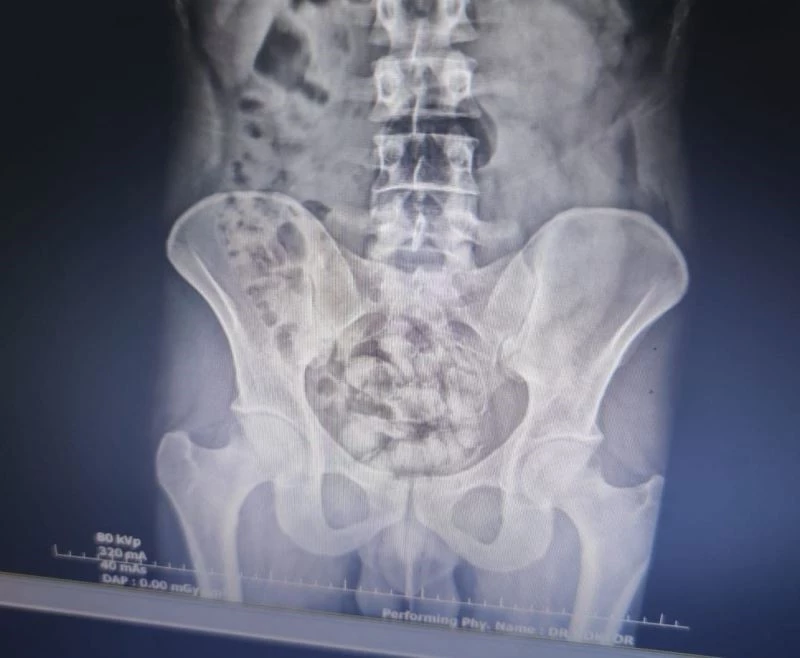

Van polisi ve MİT’in ortak düzenlediği diğer operasyonda ise İran uyruklu bir şüphelinin midesinde uyuşturucu olduğu belirlendi. İran uyruklu S.Y.’nin üzerinde yapılan aramada 23 gram metamfetamin bulunurken, şahsın iç beden muayenesinde ise midesinde 25 kapsül şeklinde 351 gram metamfetamin olduğu tespit edildi. İran uyruklu şahıs gözaltına alındı.